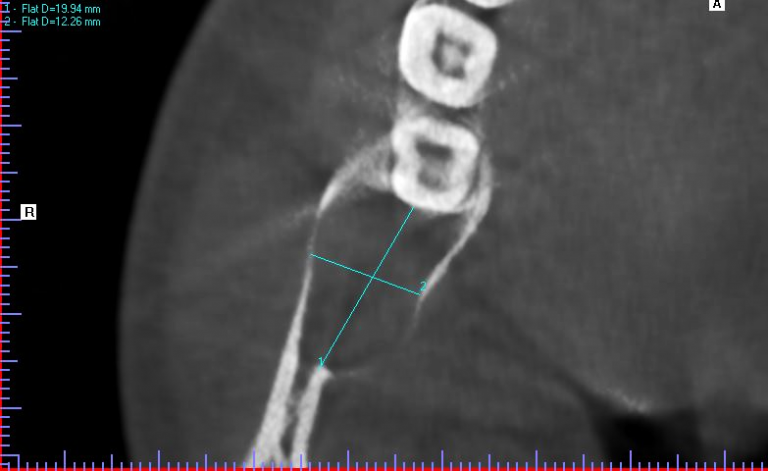

A 20-year-old male presented to our facility with a referral for a painful radiolucency of the right posterior mandible. Other than a two-year history of tobacco use, his past medical and surgical histories were unremarkable. On clinical exam, there were no mucosal changes, no palpable buccal or lingual swelling, and tooth #29, #30, #31 tested vital with no mobility, probing depths distal to #31 measured 7-8mm. On CBCT examination, the lesion exhibited a well-circumscribed, regular bordered radiolucency approximately 25mmx18mm in its greatest dimension in the right posterior mandible directly adjacent to #31. The lingual cortical plate was violated, however, the roots of tooth #31 remained intact. Additionally, the inferior pole of the lesion was contiguous with the superior aspect of the Inferior Alveolar nerve canal, but did not displace the nerve/canal (Figure 1). Tooth #32 was missing and, per patient report, had never developed. Differential diagnosis based on location and demographics included Dentigerous Cyst, Odontogenic Keratocyst, Ameloblastoma, Myxoma and Hemangioma in order of most to least likely diagnosis. After the risks, benefits and alternatives were discussed with the patient, he elected to undergo excisional biopsy under IV General Anesthesia.